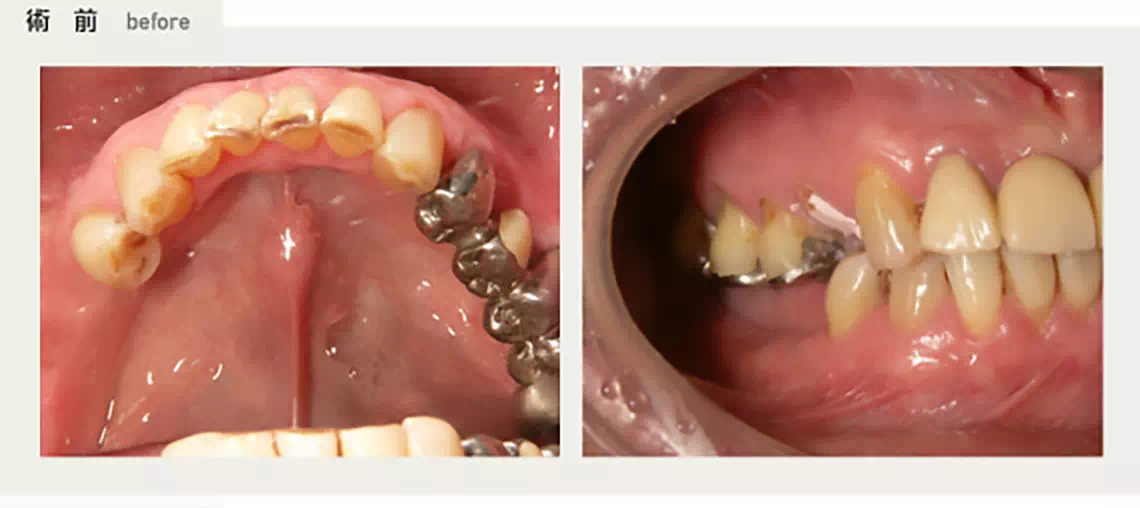

上の両側に部分的に歯が無い方 50代 女性

上の両側に部分的に欠損があり、着脱式の入れ歯を入れていましたが、上顎に右から左へ渡るバーがあり、発音しづらく、お困りでした。入れ歯の煩わしさから解放されたいとのことでインプラント治療を行いました。